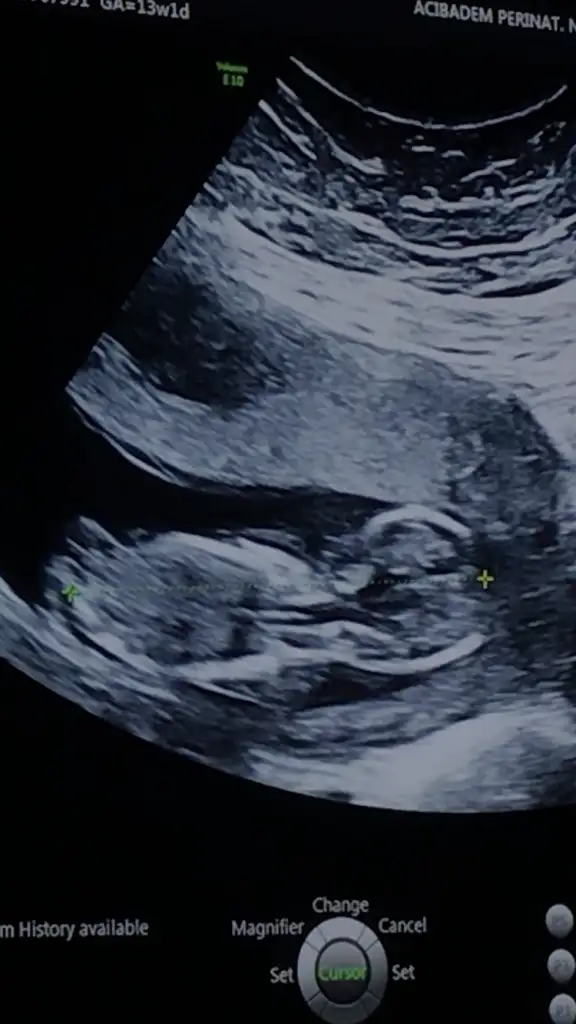

yine kız yönünde nubuMerhaba. 11. Hafta Usg paylasmistim, kiz olabilir yeniden paylasin demistiniz. Su an 13. Hafta goruntusunu ekliyorum. Tahmin alabilir miyim? Tesekkur ederim. Eki Görüntüle 2593830

yine kız yönünde nubu![]()